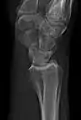

Extremities

A projectional radiograph of an extremity confers an effective dose of approximately 0.001 mSv, comparable to a background radiation equivalent time of 3 hours.[16]

The standard projection protocols in the UK are:[15]

• Hip joint: AP and Lateral.[15]

• The Lauenstein projection a form of examination of the hip joint emphasizing the relationship of the femur to the acetabulum. The knee of the affected leg is flexed, and the thigh is drawn up to nearly a right angle. This is also called the frog-leg position.

Applications include X-ray of hip dysplasia.

• Femur - AP and Lateral